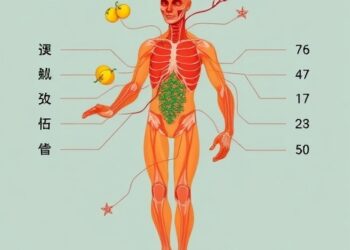

In Silico Study of Testolift Targets Testosterone Boost

In the relentless pursuit of enhanced muscle performance and optimized testosterone regulation, groundbreaking research has unveiled a multifaceted nutraceutical formulation...